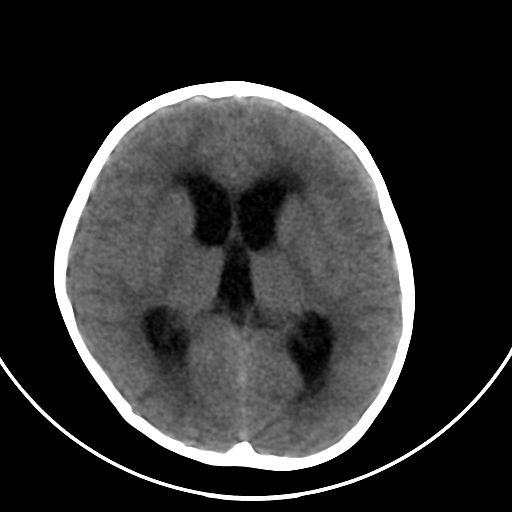

以下是引用zjzjr在2008-7-27 9:56:00的发言:[br]考虑髓母细胞瘤伴梗阻性脑积水.建议增强或mri

以下是引用子十在2008-7-27 9:53:00的发言:[br]考虑髓母细胞瘤